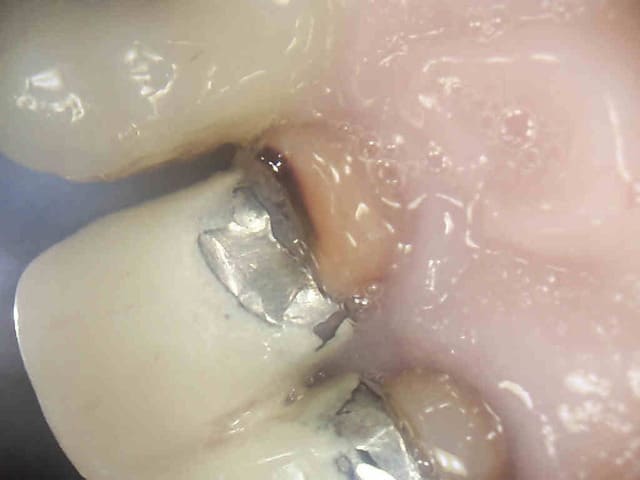

Traitement tout frais. Le patient vient pour une couronne ( question de tarifs) je reprend ou pas ?

Le traitement a trainé dans la salive, il y a une insuffisance sur les trois canaux Ne te pose pas de questions.

Avant-après. Léger mieux non ? -))))

Pour ma part, je n'aurais pas entrepris de reprendre le traitement endodontique de la molaire. Si cliniquement, il n'y a aucun symptôme, je ferais la couronne dessus, point.

Y retourner comporte beaucoup de risques: préparation plus importante, stripping, fausse voie, fracture instrumentale et j'en passe.

@Chicot29 : Pourquoi deux ancrages en mésial et aucun en distal alors qu'en distal le canal parait être dans l'axe d'insertion du futur inlay clavette?

C'est pas 2 ancrages ce sont les empreintes des machtou. -))))